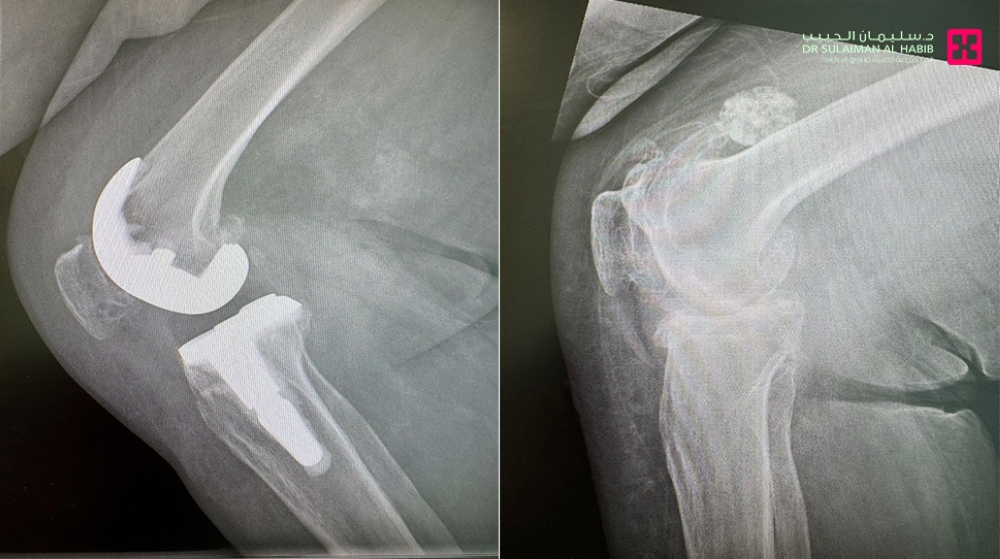

في إنجاز طبي جديد يُضاف إلى سجل المنجزات الصحية في المملكة، نجح مستشفى الدكتور سليمان الحبيب بالخبر في إجراء عملية متقدمة لاستبدال مفصل الركبة لسيدة تبلغ من العمر 77 عامًا، مستخدمًا تقنية الروبوت الجراحي (Robotic Surgery) وتحت التخدير النصفي، في واحدة من أبرز العمليات الدقيقة التي تمثل نقلة نوعية في مجال جراحات المفاصل والعظام بالمنطقة الشرقية.

بدأت القصة حين وصلت السيدة السبعينية إلى المستشفى وهي تعاني من خشونة حادة في مفصل الركبة، وتآكل الغضاريف، والتهاب في الأربطة، إلى جانب معاناتها من أمراض مزمنة متعددة مثل ارتفاع ضغط الدم، والسكري، وهشاشة العظام، وكسل الغدة الدرقية، والنقرس، واحتكاك العمود الفقري.

وأوضح الدكتور سكيك أن الفريق الطبي أجرى فحوصات دقيقة بالأشعة المقطعية والرنين المغناطيسي لتقييم حالة المفصل والأنسجة المحيطة، وتحديد خطة العلاج المناسبة قبل الجراحة.

ووفقًا للفريق الطبي، فقد تم خلال العملية تصحيح التقوس الحاد في الساق باستخدام دعامات دقيقة، وتعويض ضعف الأربطة عبر تثبيت المفصل الصناعي عالي الجودة، الذي صُمم خصيصًا ليتناسب مع قياسات المريضة.